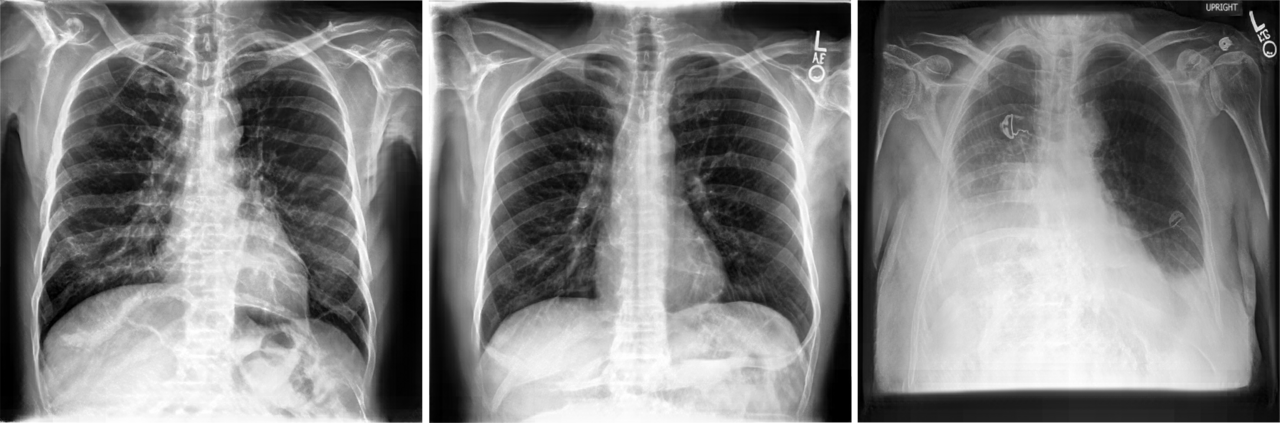

Figure 3:

(a.) Synthetic chest x-rays and (b.) closest matching real nearest neighbours at a resolution of 512 x 512 pixels

The quality of the chest x-rays in Fig. 3 also appears to be close to the quality of real data, without simply copying training images. However, for the support devices class, we observe visual artefacts in the synthetic x-rays. The GAN model fails to realistically generate tubes and other support devices, such as pacemakers or defibrillators, as shown in Fig. 4. These devices deviate strongly in their visual appearance when compared to the physiological chest outlining and were not accurately learned by the generative model. Crucially, our benchmark successfully captured the drops in visual quality due to the support devices class at higher resolutions.